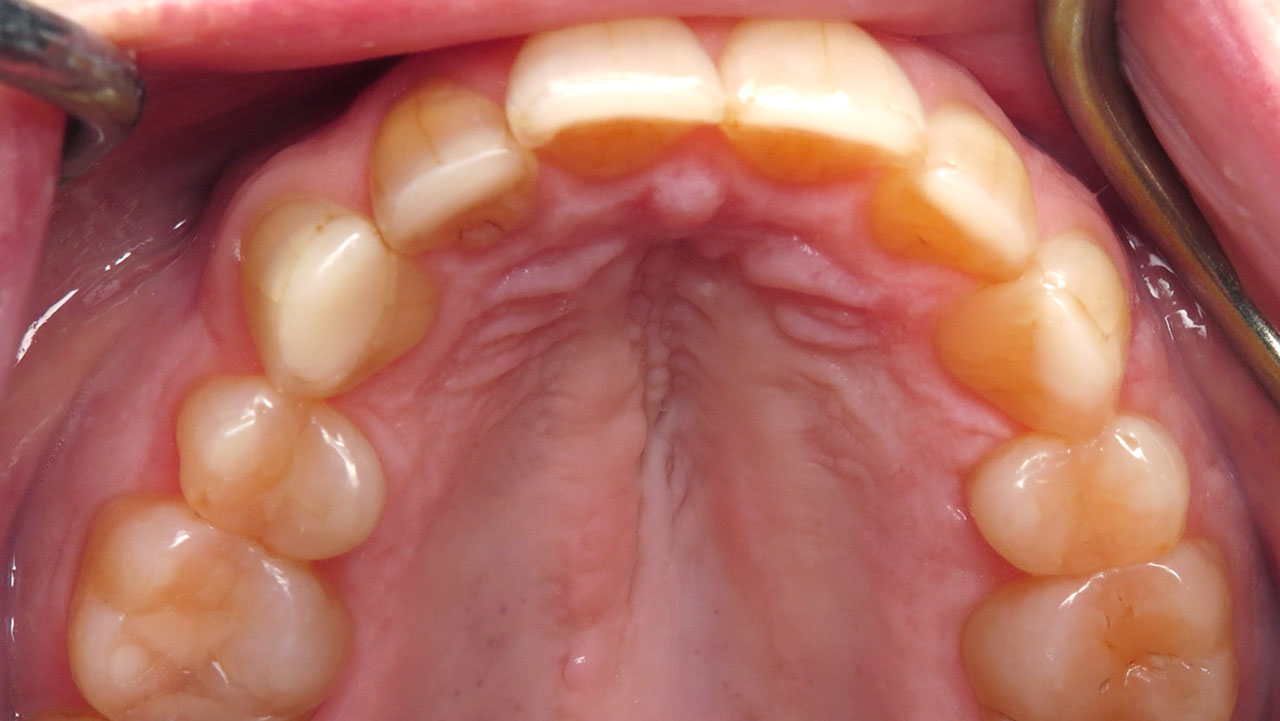

Removal of early decay and conservative bonding to restore the worn edges of the upper and lower front teeth.

Conservative composite bonding on six upper and six lower front teeth.

The worn edges were restored to a smoother, more protective shape, improving function while protecting exposed dentin and early decay areas.

Treatment focused on removing the decay and conservatively restoring the worn edges of both the upper and lower front teeth. Composite bonding was used to rebuild the edges of twelve teeth so they could function more smoothly against each other while protecting the exposed dentin.

The treatment was completed over two visits and required no local anesthesia. Afterward, the patient was surprised by how much she liked the way her teeth looked, felt, and functioned.